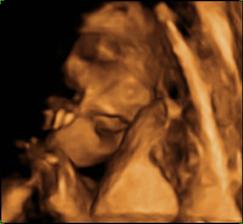

Moj prvy tehulkovsky